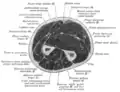

- Cross-section through the middle of upper arm.

- Cross-section through the middle of the forearm.